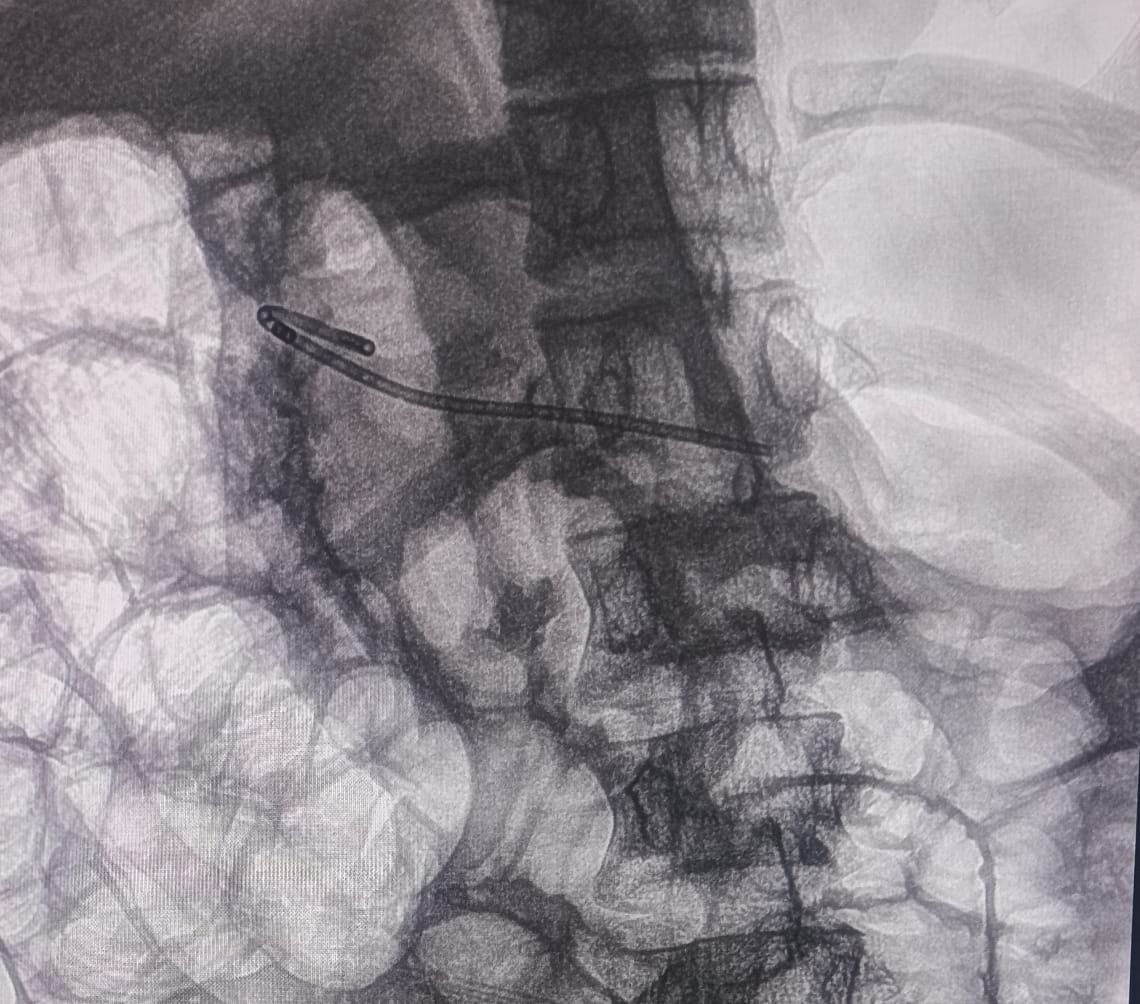

A pinpoint major papilla was noted. PD cannulation was achieved from the minor papilla and dye was injected. The PD was found to be dilated in body and tail up to 5.6mm.

Communication of duct of Santorini was found to be of very small caliber. Cannula was passed into the pancreatic duct of body and tail. Duct of Santorini was dilated up to 4mm with biliary hurricane balloon. A 7Fr x 7cm single pigtail pancreatic stent was placed in the PD.

Chronic Pancreatitis ERCP Image 2

Minor Papilla Cannulation

Chronic Pancreatitis ERCP Image 3

Balloon Dilation

Chronic Pancreatitis ERCP Image 4

Stent Placement